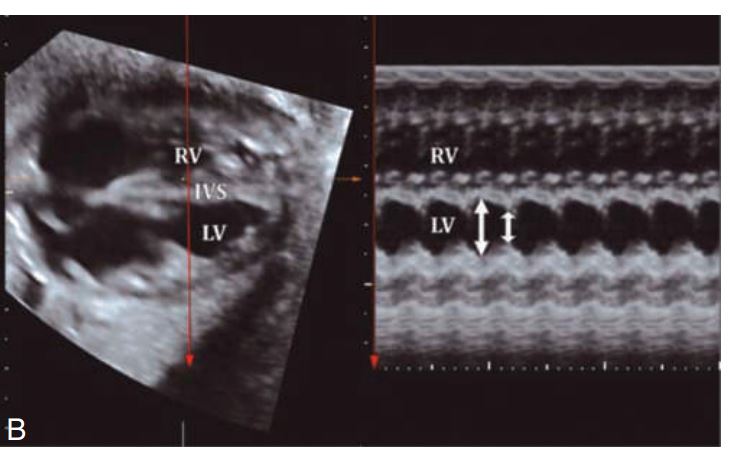

Two-dimensional and M-mode image demonstrating

pericardial effusion.

The fetal heart must be monitored to rule out congenital _________ (Fig. 54.18) and pericardial effusion.

heart block